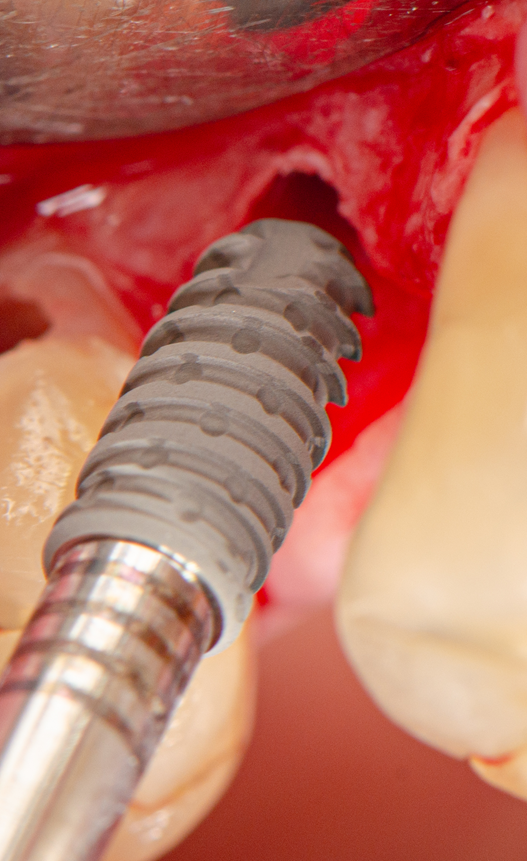

Técnica cirúrgica

Sob anestesia local, realizou-se incisão crestal na área edêntula do dente 16. O sítio foi marcado com broca lança e fresado conforme protocolo Implacil Osstem para implantes de 4,0 mm. O implante Maestro Superiore 4,0 × 9 mm foi instalado, apresentando torque progressivamente elevado até a posição final, com plataforma 2 mm infraóssea. O torquímetro registrou 50 Ncm, confirmando excelente estabilidade primária, condição favorável para carga precoce ou imediata, em linha com a literatura que destaca a alta fixação inicial dos implantes Maestro sem comprometer o osso circundante.

Acoplou-se imediatamente um cicatrizador ao implante, afim de facilitar o momento de reabertura e foi realizada a sutura.